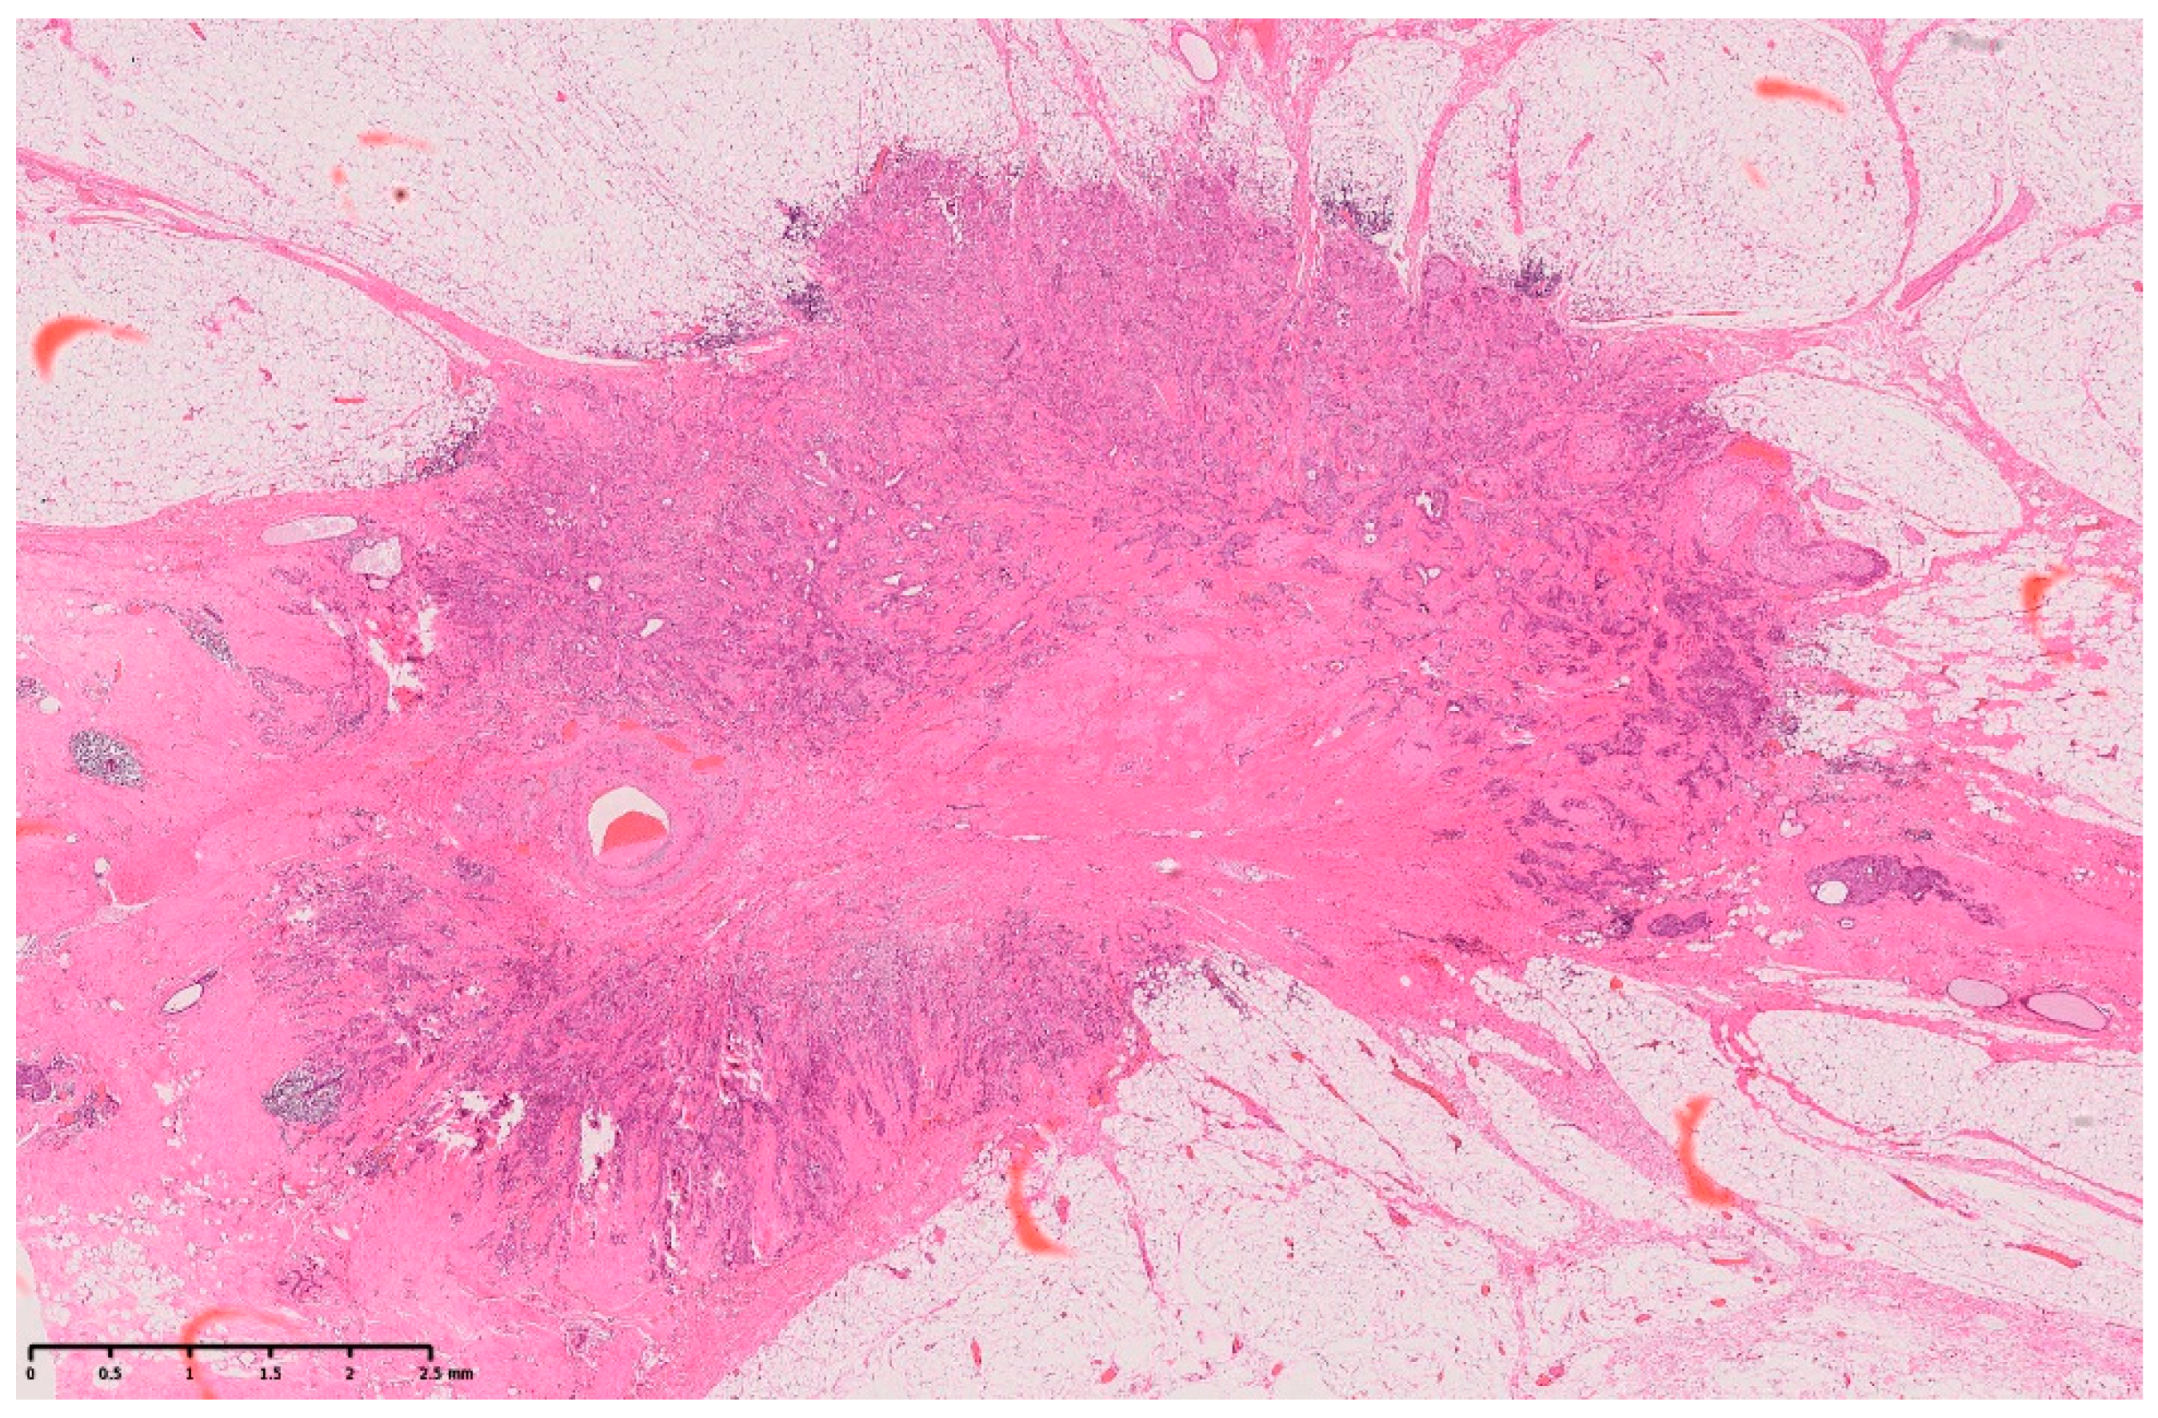

Arterial Calcification Disappearance in Breast Imaging: A Key Indicator for Transition to Invasive Ductal Carcinoma

Sato, A.; Fujioka, T.; Onishi, I.; Yamaga, E.; Katsuta, L.; Kubota, K.; Kumaki, Y.; Ishiba, T.; Oda, G.; Tateishi, U. Arterial Calcification Disappearance in Breast Imaging: A Key Indicator for Transition to Invasive Ductal Carcinoma. Diagnostics 2024, 14, 727. https://doi.org/10.3390/diagnostics14070727